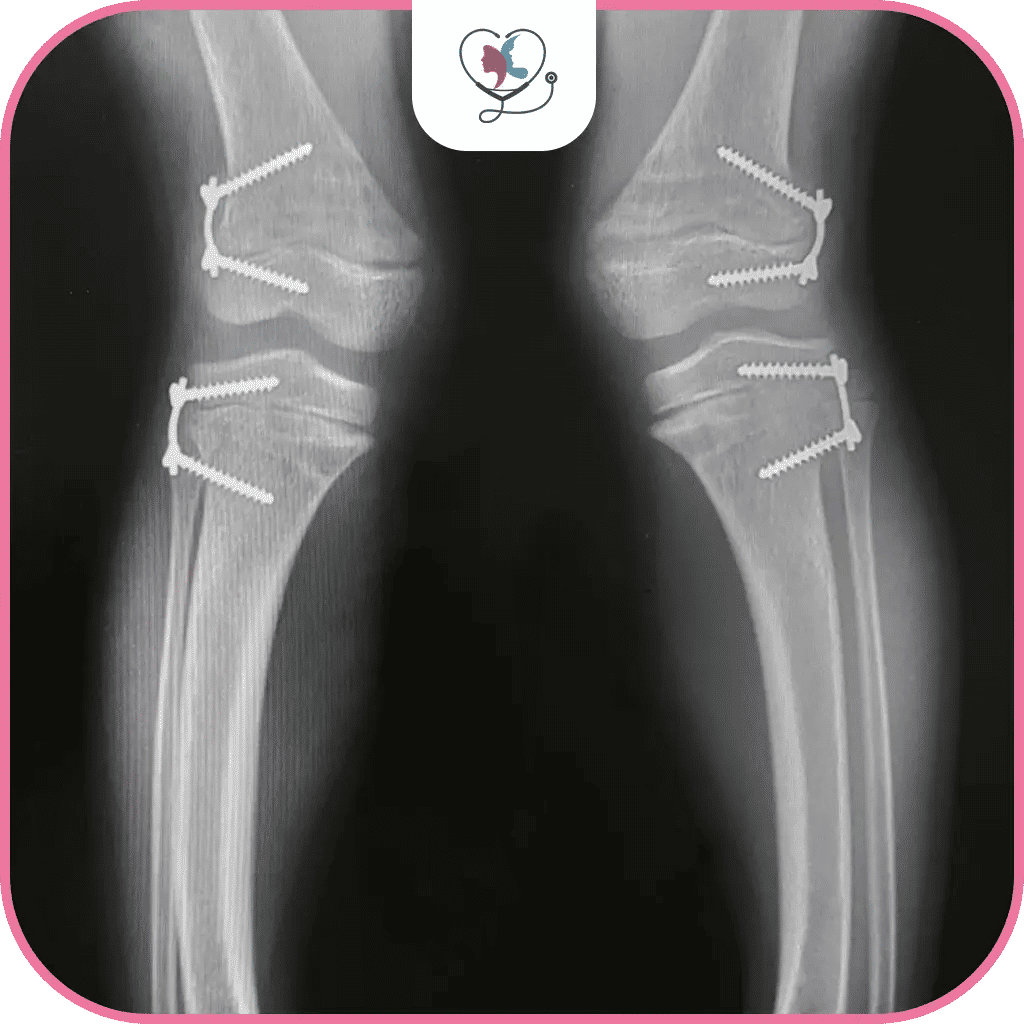

ثانياً: قطع عظم الظنبوب Tibial Osteotomy

غالباً ما يتم هذا الإجراء في عملية تقوس الساقين للكبار ولكنه قد يكون مناسباً للأطفال أيضا!! حيث يقوم الجراح بقطع عظم الساق "عظمة الظنبوب" ويعيد تصحيحه بالكامل لتحسين التقوس والحصول على ساقين متناسقتين، ويقوم بتثبيت العظم بعد تصحيحه بوساطة مسامير وصفائح معدنية لمدة 8 أسابيع، وعلى العكس النوع السابق؛ فإنّه لن يسمح للمريض بالسير على قدميه خلال هذه الفترة للحفاظ على التثبيت وعدم تخرب التصحيح الذي قام به الجراح.

3. العملية الجراحية

- شق جراحي: يقوم الجراح بعمل شقوق صغيرة في الجلد للوصول إلى العظام.

- قطع العظم أو تعديل النمو: حسب نوع العملية، يقوم الجراح بقطع العظم وتصحيح زاويته أو إبطاء نمو جانب واحد من العظم.

- تثبيت العظم: يتم تثبيت العظم باستخدام صفائح ومسامير معدنية أو جهاز خارجي.

- إغلاق الشقوق: يقوم الجراح بإغلاق الشقوق الجراحية بالغرز أو الدبابيس.